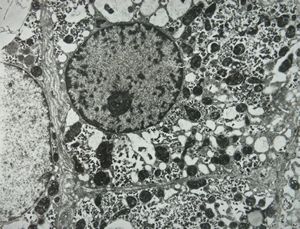

F,61y. | giant cell hepatitis - nuclear pseudoinclusion

F,61y. | giant cell hepatitis